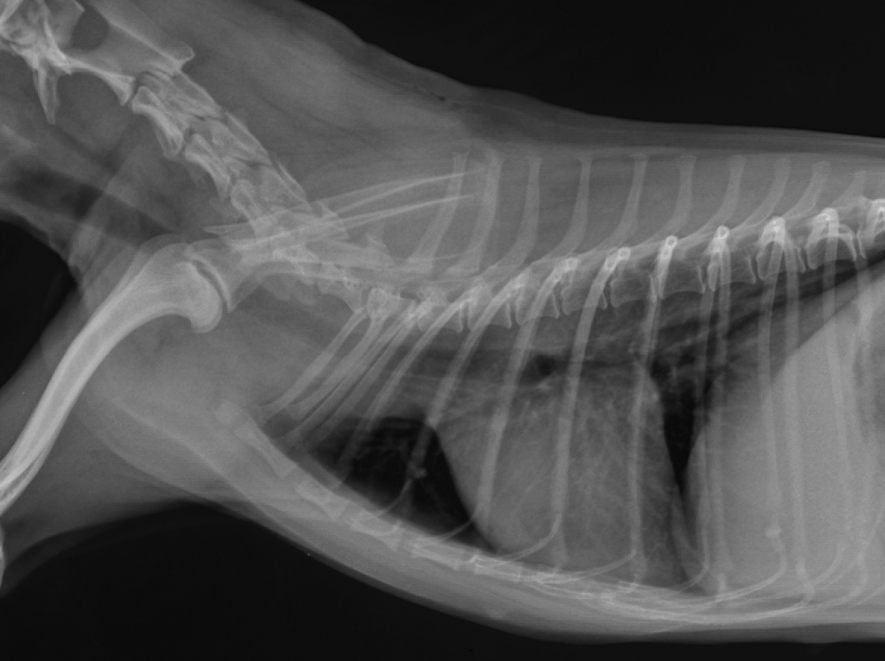

자궁 내의 고름 때문에 자궁이 팽창하고 있고, 체내의 염증치도 꽤 높은 상태입니다.

생식기 쪽으로 고름이 나오지 않는 폐쇄형 자궁축농증의 경우 고름이 자궁내부에 축적되어도 외부에서 육안으로 판별하기 어려우며, 전신의 염증이 심하게 퍼진 후 혹은 자궁파열 후에 병원을 찾는 아이도 있습니다.